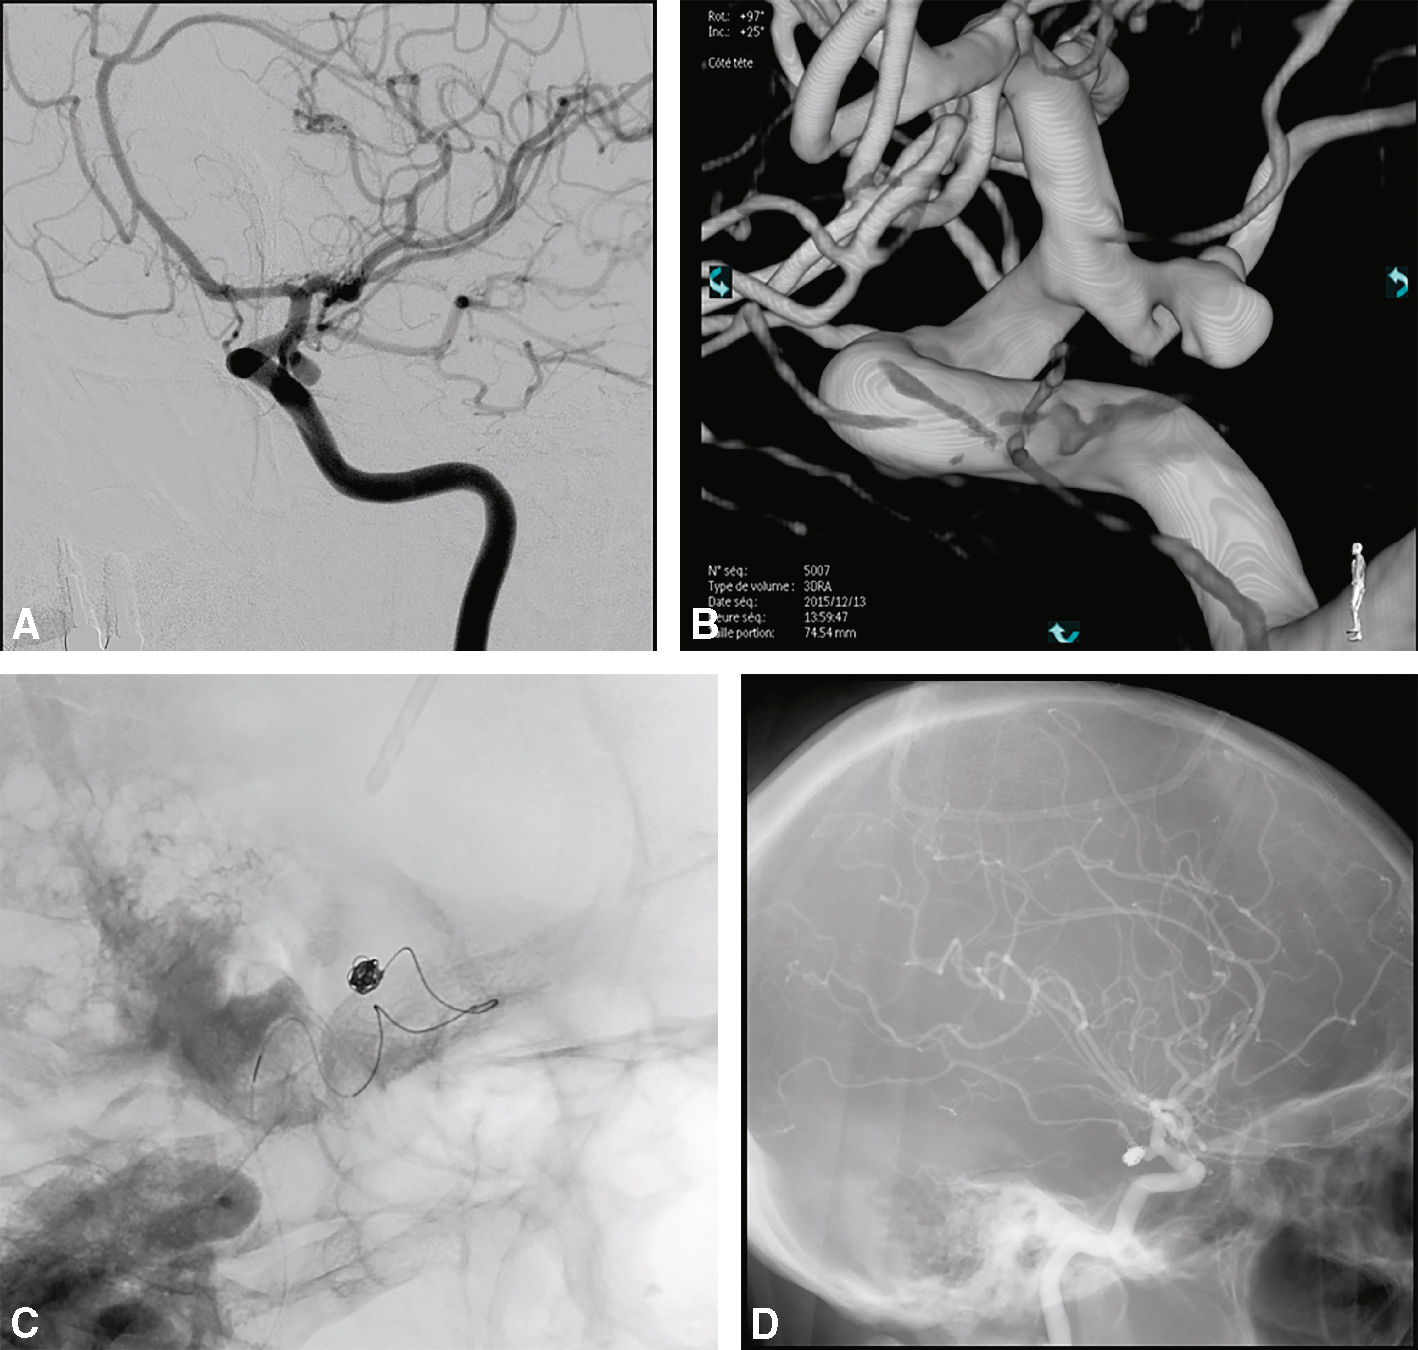

- • Exclusion précoce de l’anévrisme intracrânien dans les 24 à 48 heures qui suivent l’hospitalisation (et le plus précocement par rapport à la rupture). En cas de resaignement, la mortalité peut atteindre 60 %.

• Traitement de l’anévrisme : deux types de traitement :

- – le traitement chirurgical;

- –

le traitement endovasculaire (ou embolisation) : il est le traitement de première intention des anévrismes rompus.

Fig. 29.5

Angiographie conventionnelle (temps artériel) : anévrisme de la communicante postérieure gauche (A), image 3D (B), pendant (C) et après l’embolisation (les clichés montrant l’exclusion de l’anévrisme : D).Cette série d'images montre des étapes différentes de traitement des anévrismes intracrâniens dans le communicateur postérieur gauche. Cette photographie est une dilatation d'anévrisme bien définie dans la partie proximale du communicateur postérieur gauche, conservée par l'angiographie conventionnelle de l'âge artériel. Dans la reconstruction 3D, avec une reconstruction très précise, la figure B montre la morphologie complexe de l'anévrisme, le collier et la relation avec les branches artérielles adjacentes. La figure C illustre les étapes d'embolisation procédurale dans lesquelles la mise en œuvre en spirale (spirale) se distingue sous le contrôle scortique du rayonnement du sac d'anévrisme. Enfin, les images des résultats finaux après embolisation sont présentées avec l'exclusion complète des anévrismes dans la rivière circulatoire, indiquant le succès du traitement endovasculaire. Ce processus démontre la précision et l'efficacité de la neuroradiologie interventionnelle dans la prévention de la destruction de l'anévrisme.